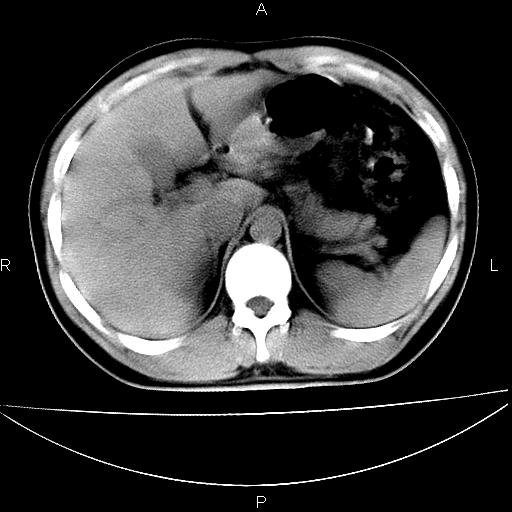

男 25岁 自述 尿频尿急,排尿困难20多天.无腰痛, b超说左肾盂轻度积水,左输尿管上端扩张.未见结石影. ct我看双侧肾盂轻度积水,双输尿管上端都扩张,大家看看能看见结石吗?

双输尿管扩张下端未见高密度结石和输尿管晕轮征,不好说是结石.增强后如何?

双侧输尿管上端扩张,未见明确结石,可进一步ivp检查。

考虑肾外肾盂 前列腺轻度肿大 密度欠均 考虑炎性改变